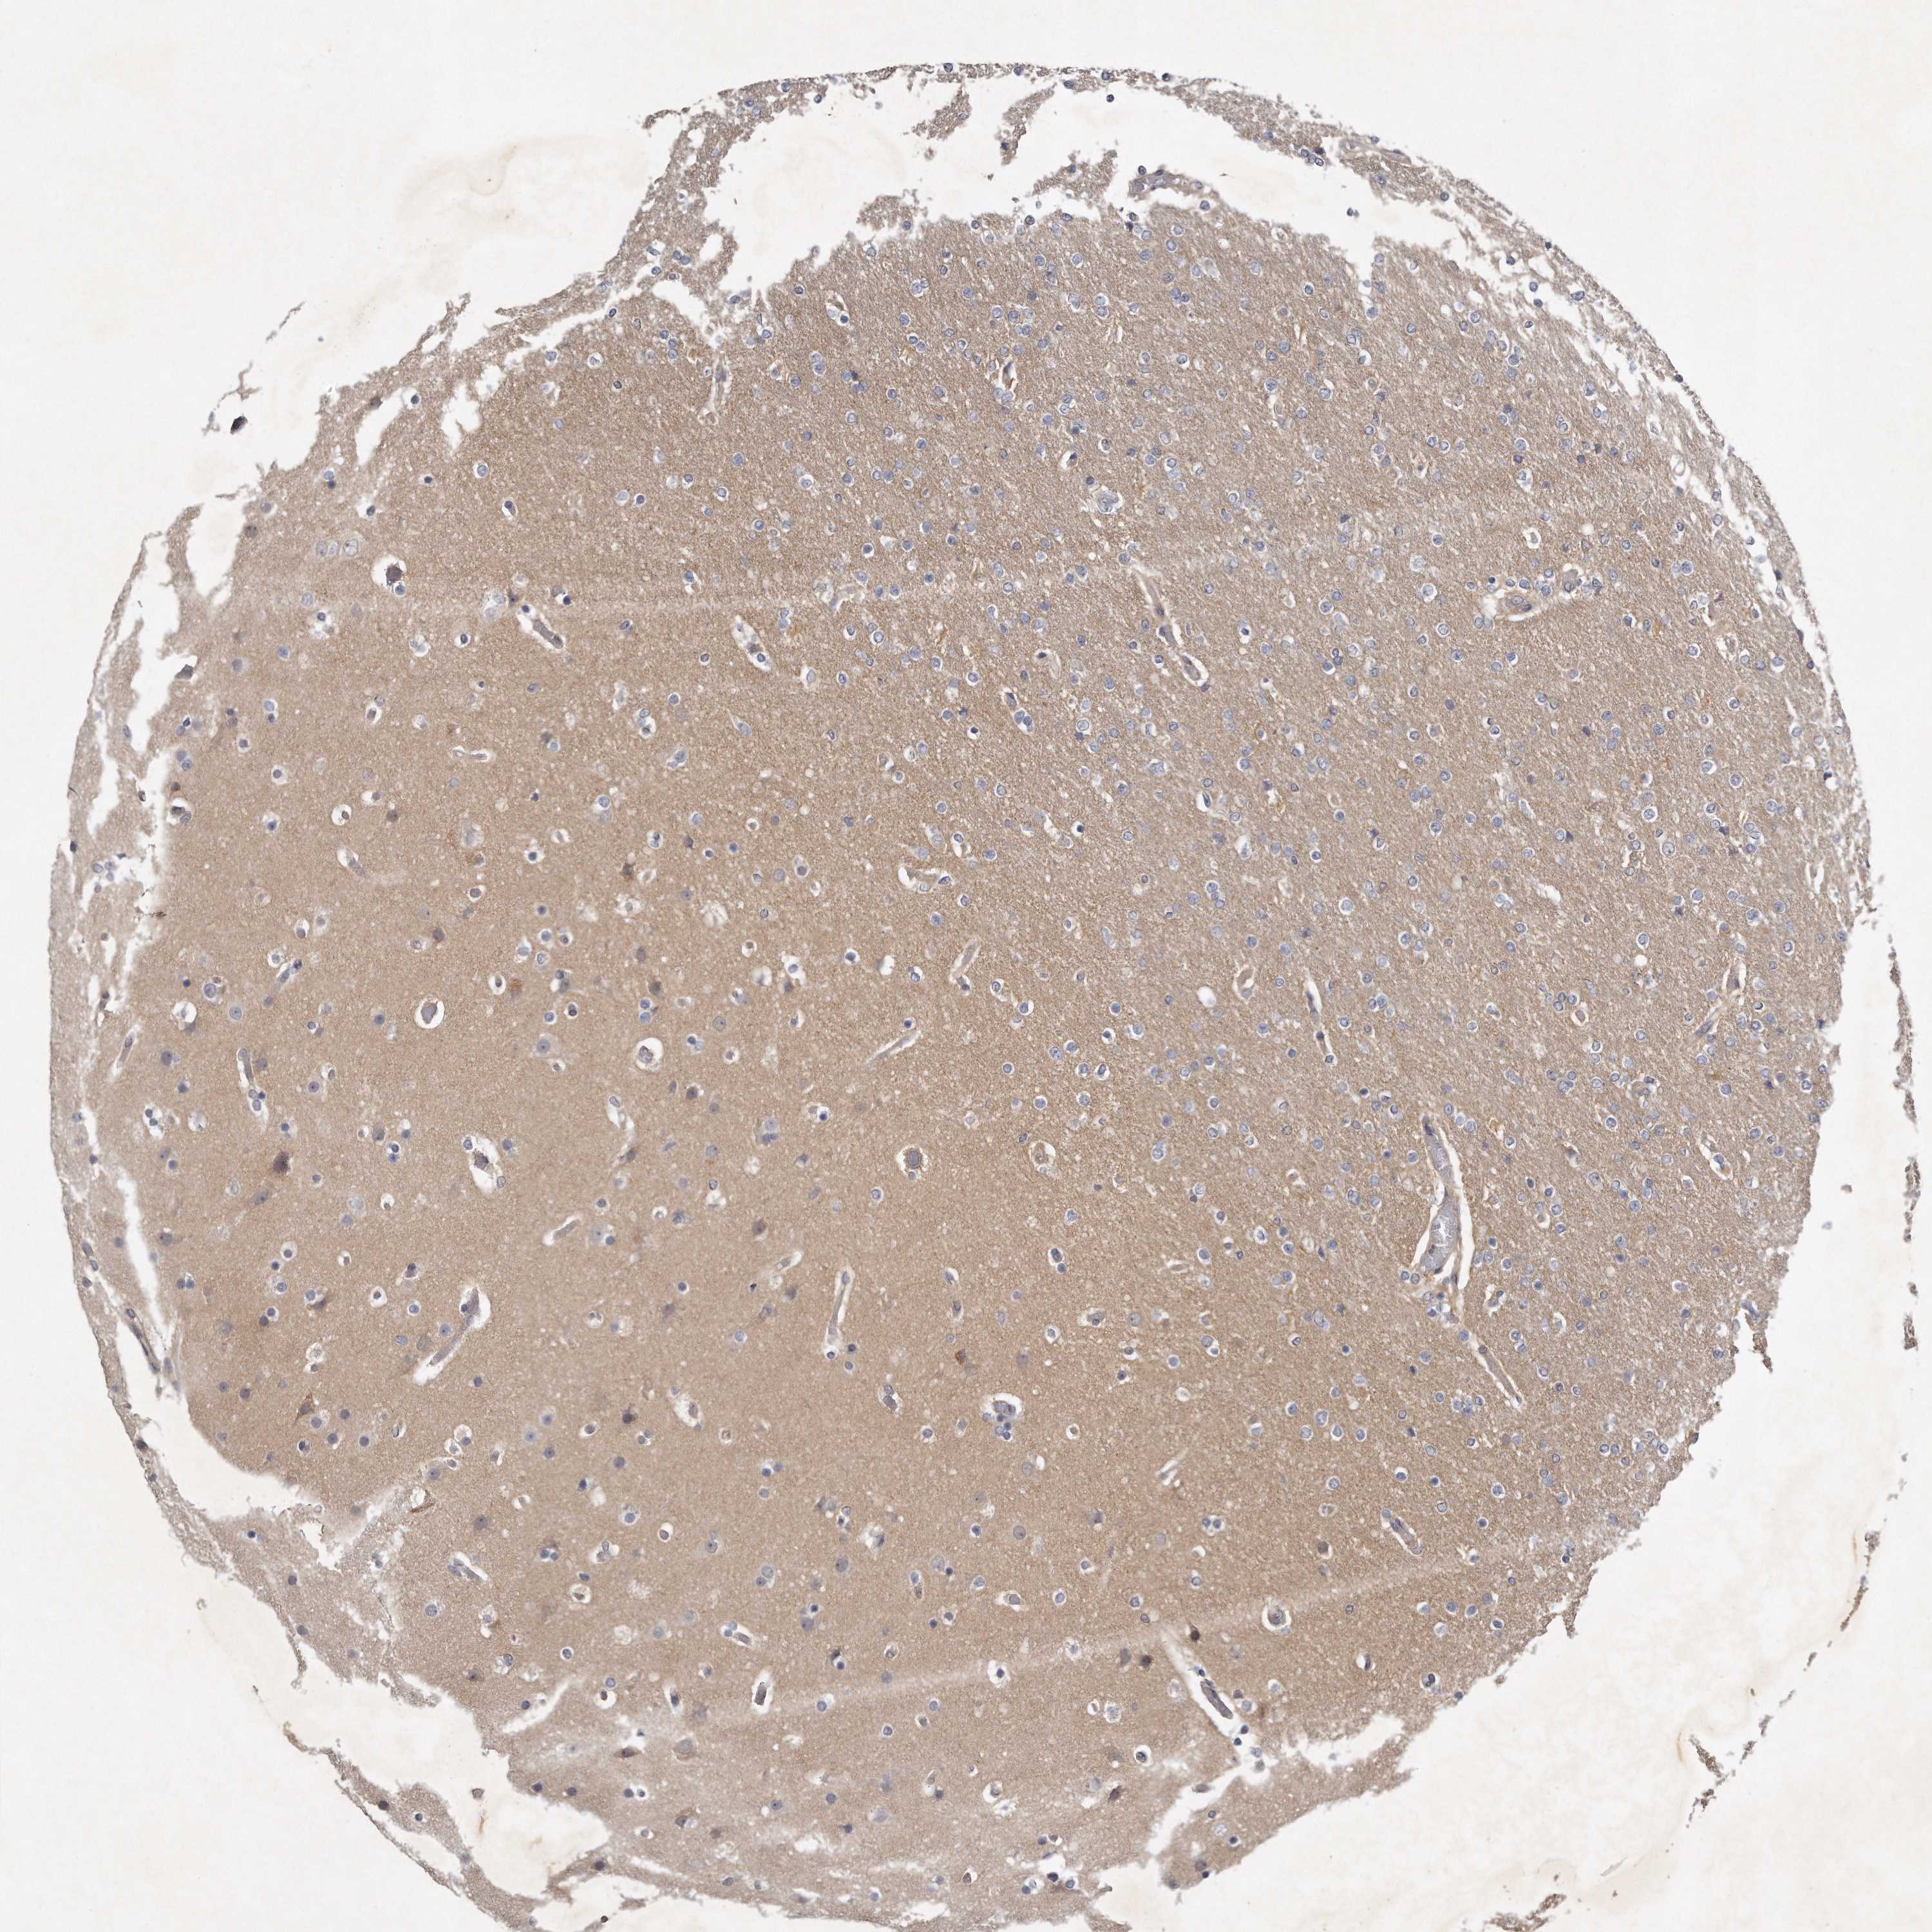

GLIOMA - Protein expressioni

A mouse-over function shows sample information and annotation data. Click on an image to view it in a full screen mode. Samples can be filtered based on level of antibody staining by selecting one or several of the following categories: high, medium, low and not detected. The assay and annotation is described here.

Note that samples used for immunohistochemistry by the Human Protein Atlas do not correspond to samples in the TCGA dataset.

Antibody stainingi

Antibody staining in the annotated cell types in the current human tissue is reported as not detected, low, medium, or high, based on conventional immunohistochemistry profiling in selected tissues. This score is based on the combination of the staining intensity and fraction of stained cells.

Each image is clickable and will lead to virtual microscopy that enables deeper exploration of all samples and also displays staining intensity scores, fraction scores and subcellular localization as well as patient and tissue information for each sample.

Antibody HPA020735

Antibody HPA029914

Staining

High

Medium

Low

Not detected

Intensity

Strong

Moderate

Weak

Negative

Quantity

>75%

75%-25%

<25%

None

Location

Nuclear

Cytoplasmic/membranous

Cytoplasmic/membranous,nuclear

Glioma, malignant, High grade

Glioma, malignant, Low grade

Glioblastoma, NOS